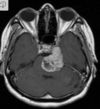

A

Cisto epidermóide

Hipersinal na difusão

Sinal heterogêneo no FLAIR

Extra-axial

Cisto epidermóide do SNC

Sinal heterogêneo no FLAIR e Hipersinal na DWI

Extra-axial nas sisternas da base.

355

Cisto epidermóide do SNC Sinal heterogêneo no FLAIR e Hipersinal na DWI Extra-axial no angulo pontocerebelar